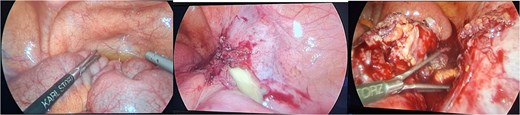

The patient was admitted, and he underwent an emergency laparoscopic appendectomy with partial cecectomy, mesenteric mass excision, and peritoneal lavage. Intra-operative findings included a gangrenous perforated appendix with a right pelvic pus collection, which was aspirated and sent for culture (Fig. 4). A mesenteric mass measuring 6 × 4 cm was noted ⁓70 cm away from the ligament of Treitz distally and excised (Fig. 5). The surgery was completed without complications.

Intra-operative findings included a gangrenous perforated appendix with a right pelvic pus collection.